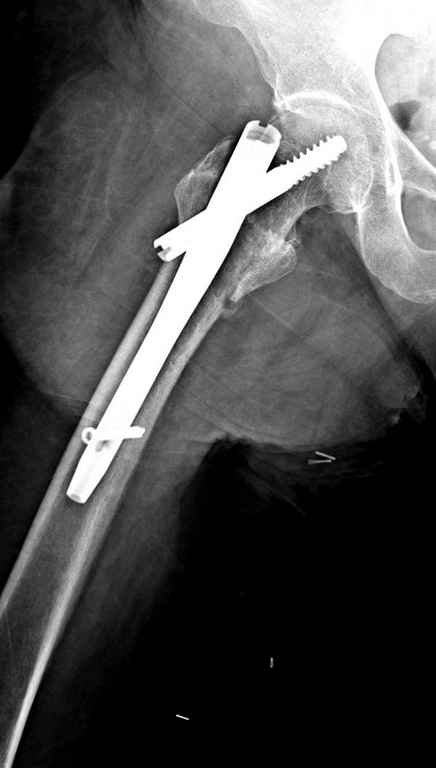

В приложении похожий пример, к счастью, пациентка появилась не после, а "за полчаса" до протрузии. Пересинтезировали с исправлением ошибок.

В данном случае в головке бедра и в вертлужной впадине огромный дефект, навряд ли удалением импланта или заменой на другой можно сохранить сустав.

Вашему вниманию представляется похожий случай, пациентке 70, осложнился в течение одного месяца после операции. Ревизия с заменой сустава, кабельная фиксация на трохантер. При установке в дистальном диафизе обнаружен тонкий кортикальный слой и сделана профилактика от возможного перелома аллографтом.